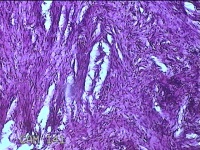

前胸部包块

性别

女

年龄

45岁

临床诊断

皮脂腺囊肿

一般病史

发现前胸部包块3个月余。

标本名称

大体所见

灰白暗红色组织2.2x1x0.8cm一块,表面带梭形皮肤2.2x1.3cm,皮下见包块1.8x1.2x0.8一块,切开包块呈实性,切面灰白粉红色,质软。

图2